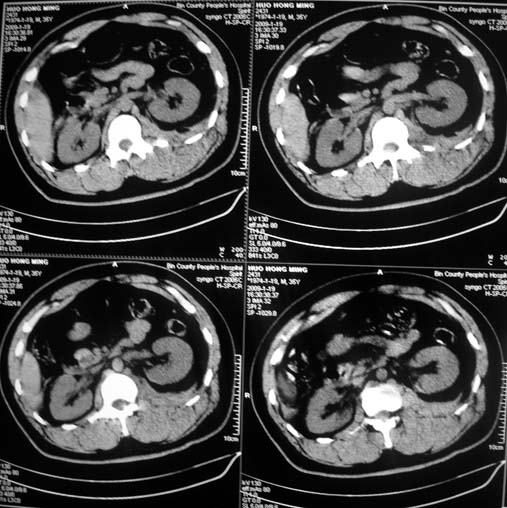

以下是引用余辉在2009-1-20 8:22:00的发言:[br]右侧肾上腺明显增大、边缘不光整,肯定有问题,结合患者病史考虑肾上腺挫伤、伴血肿形成。[br]另左肾后唇包膜下方可见局限性新月形高密度影,考虑肾包膜下出血[br]余同意楼上,建议增强排除脾破列

以下是引用随光逐影在2009-1-20 8:21:00的发言:[br]1)左侧多发肋骨及部分腰椎左侧横突骨折。2)左侧肾旁后间隙及同侧胸腔积血。3)左侧腰大肌肿胀。